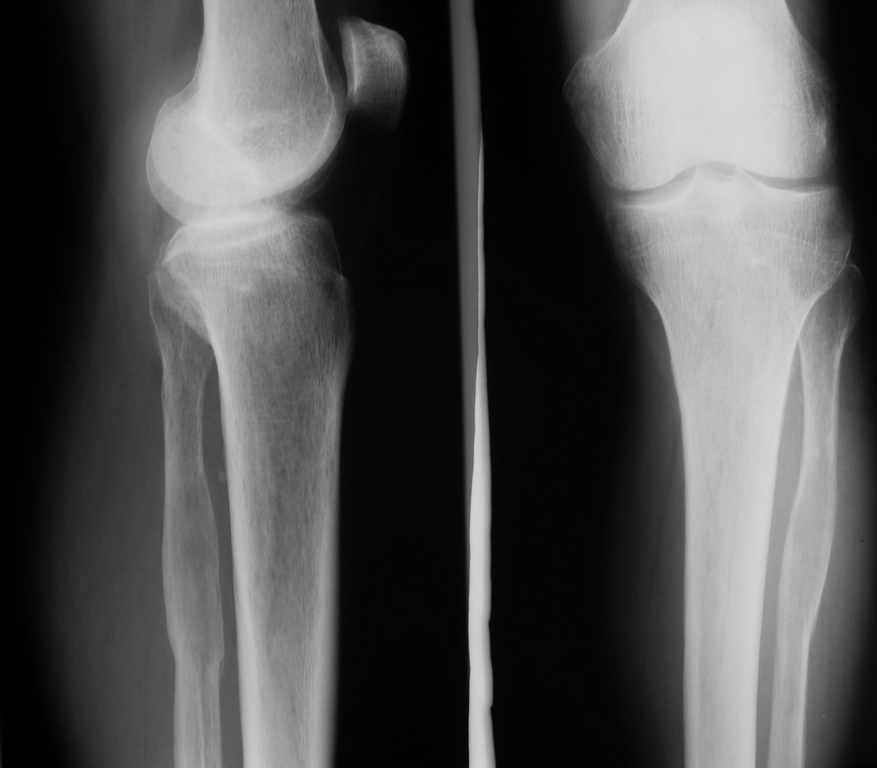

Ещё одно клиническое наблюдение - лимфома кости, до и после ПХТ и лучевой терапии.

Мамонов Василий Евгеньевич, ГНЦ РАМН